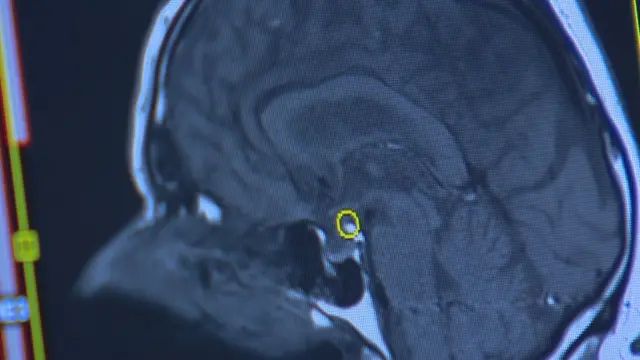

آنها دریافتند که تغییرات ژنتیکی روی قسمتهایی از ارتباطات عصبی مغز تاثیر میگذارد که در تصمیمگیری و شخصیت افراد نقش دارد و آن را کنترل میکند.